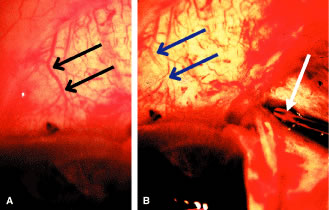

In the later stages of the disease, one can be fairly sure about whether the optic nerve is glaucomatous or not. By later stages of the disease is meant a situation in which there is absence of rim tissue in one area of the optic nerve, especially supertemporally or inferotemporally. However, in the early stages of glaucoma it is not possible on the basis of a single examination to determine whether the optic nerve is damaged. For example, a patient with a central cup and a rim/disc ratio of approximately 0.3 in all areas could have an optic nerve that has improved, remained the same, or gotten worse (Fig. 2). Consequently, in the early stages of the disease it is impossible to determine whether an optic nerve head is healthy or diseased on the basis of a single ophthalmoscopic or image analysis examination. On the other hand, it is possible with a high degree of reliability to look at such an optic nerve and determine whether or not a visual field defect is present. Normal-sized discs (around 1.75 mm) with rims thicker than 0.1 rim/disc ratios rarely have visual field loss. Small discs, that is, discs that are smaller than 1.5 mm in diameter, will rarely have visual field defects when the rim/disc ratio is greater than 0.2. Obviously, if no visual field defect is present, it is unlikely that the patient will have any disability as a result of any change that has already occurred in the optic nerve. Thus, even though it is not possible to look at an optic nerve without an acquired pit of the optic nerve, a notch, or complete loss of the neuroretinal rim all the way to the outer edge of the rim and determine with certainty whether or not the disc is damaged, it is possible to determine whether such a disc will be associated with any functional loss of vision.

Fig. 2. It is impossible to determine whether a disc is damaged when it is in the early stages of damage. A. A disc with a rim/disc ratio of 0.4 in a patient who has actually gotten worsen. This can be seen by examining illustration B, which is a prior photograph of the optic nerve with a rim/disc ratio of 0.3. This, however, also represents actual deterioration from a previous state, as shown in C, which depicts the optic nerve in its healthier condition. (Spaeth GL (ed). Glaucoma. In Tasman W, Jaeger EA (eds). The Wills Eye Atlas of Clinical Ophthalmology. Philadelphia: Lippincott-Raven, 1996.)